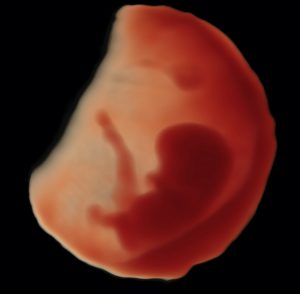

Echographies Obstétricales et Gynécologiques

ÉCHOGRAPHIE OBSTÉTRICALE